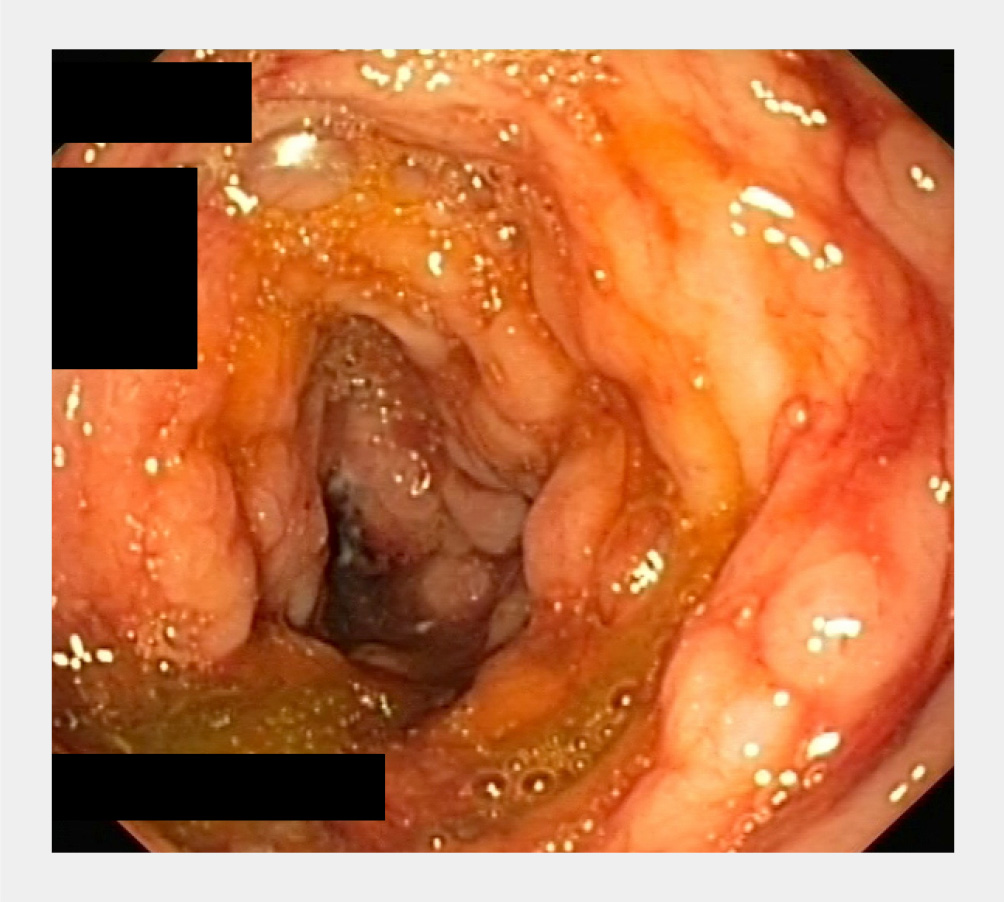

Bij coloscopie zagen wij ulceraties in het colon (figuur 1). Histopathologisch onderzoek van biopten uit het colon gaf aanwijzingen voor amoebeninfectie. De uitslagen van serologisch onderzoek en PCR op feces waren eveneens positief voor E. histolytica . Er bleek dus sprake te zijn van een invasieve amoebeninfectie. De behandeling met azathioprine en sulfasalazine werd gestaakt en vervangen door een kuur metronidazol (750 mg 3 dd gedurende 7 dagen), gecombineerd met clioquinol 250 mg 3 dd gedurende 10 dagen. Hiermee werd de patiënt klachtenvrij.

Figuur 1

Ulceraties in het colon bij patiënt A

Figuur 1 | Ulceraties in het colon bij patiënt A

Beeld bij coloscopie. Histopathologisch onderzoek van biopten uit de colonwand was suggestief voor amoebeninfectie, een diagnose die later bevestigd werd met serologisch onderzoek en PCR.